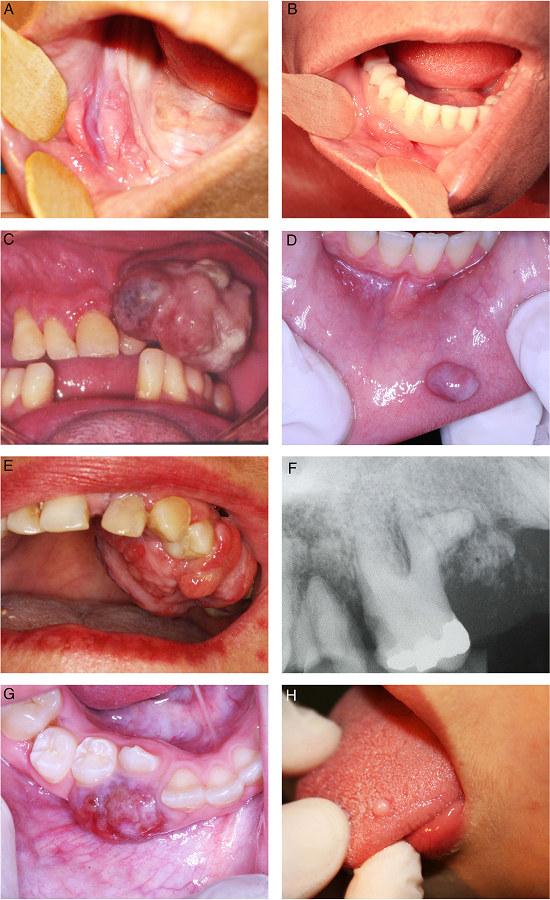

During the 10 years period, 2400 cases of oral lesions were biopsied and examined histologically at the Oral Pathology Laboratory. From this total, 534 cases were diagnosed as RHL, with an incidence of 22.25%. Fig. 1 illustrates the general incidence of lesions recorded as it relates to the histologic type. These cases occurred more frequently in females (74.19%), with the exception of PGCL which was the only group of lesions that demonstrated a higher incidence (61%) in males (Table 1). Amongst the women affected, 11.11% of the OPG cases were related to pregnant women. The patient age varied widely (Table 2). The preferential anatomic location was the alveolar ridge and jugal mucosa (Table 3). The recorded lesions were usually nodular, with the sizes ranging from 0.5 cm to 2 cm, resembling the color of the mucosa or slightly reddish-purple (Fig. 2). In all cases, the main etiological factor was ill-fitting dentures (Fig. 2B); excluding POF which presented the bacterial plaque as the main reported factor (Table 4).

In general, the correlation among clinical and histopathological diagnoses was high; 370 out of 385 RHL's lesions received the same diagnosis from a clinical examination and a histopathologic exam. However, this concordance widely varied according to the lesion type; the higher concordance was observed in IFH lesions (96%), while GCF (7%) was lower (Fig. 3). Detailed information regarding histopathological features can be found in Fig. 4. And all detailed demographic data are reported in Tables 1-4.